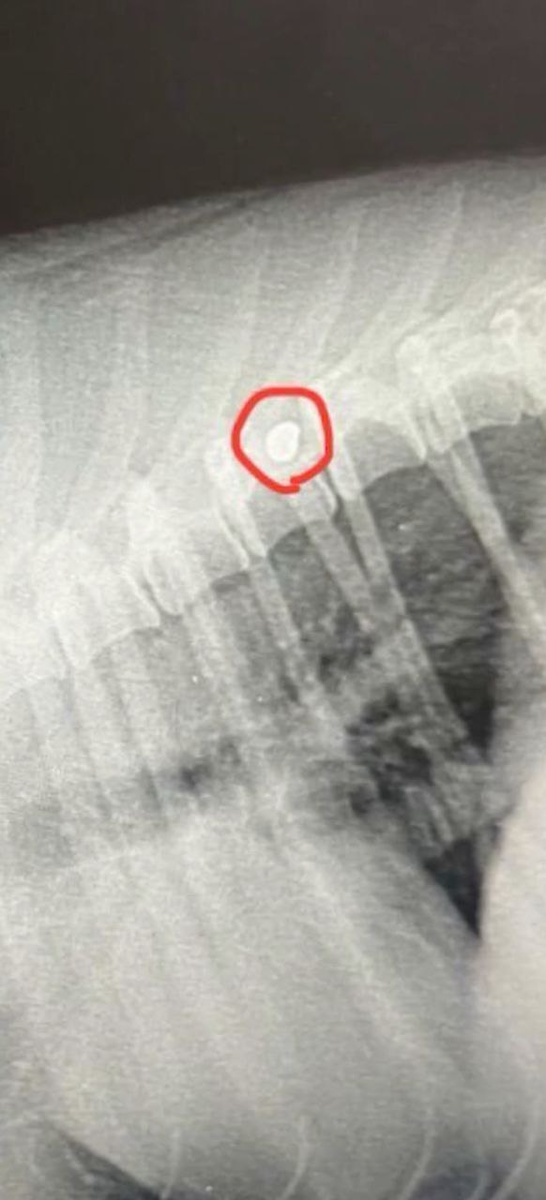

В бесплатную ветсанчасть «Верность» поступил пес с пулевым ранением в позвоночнике. Малыша подобрал мужчина на трассе в Орловской области, заметивший несчастное животное. Травма от выстрела не позволяет собаке нормально передвигаться — она может ходить только с помощью передних лап. Добровольцы отвезли бедолагу на прием к ветеринару. После осмотра стало понятно, что пуля попала в спинной мозг и давит на область спинномозгового канала. Диагноз, поставленный псу, — компрессия спинного мозга. Возможно, рядом есть серьезная гематома. При этом чувствительность задних лап сохраняется. «Врач принял решение — извлечь пулю из позвоночника. Это даст шанс Орлу встать на ноги! Вероятно, он сможет снова ходить! Если пулю не извлечь, она обрастет костной мозолью, что создаст определенные проблемы в области позвоночника и собака может остаться инвалидом навсегда», — рассказали добровольцы приюта. Ранее наше издание писало, что смоленские волонтеры пытаются спасти аистенка с поломанным крылом.

Фото: Верность Елена Воронцова